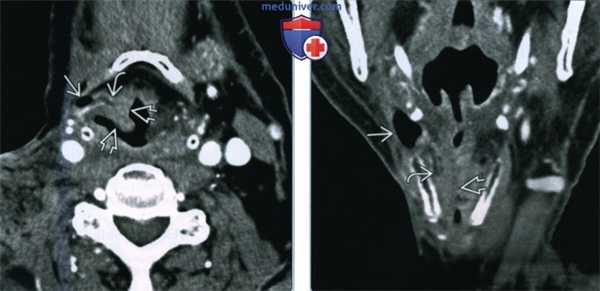

(Слева) При аксиальной КТ с КУ визуализируется смешанное вторичное ларингоцеле заполненное газом, со «стебельком», заполненным жидкостью. Ларингоцеле обусловлено обструкцией желудочка гортани опухолью (ПКР) ее преддверия, накапливающей контраст. Опухоль распространяется на ложную голосовую складку и обусловливает увеличение черпалонадгортанной складки.

(Справа) При корональной КТ с КУ у этого же пациента визуализируется наружное вторичное ларингоцеле, заполненное газом, вытянутый «мешок», заполненный жидкостью, а также опухоль (ПКР) преддверия гортани и собственно гортани. У всех взрослых пациентов с ларингоцеле, выявленном на КТ, необходимо исключить ПКР гортани.